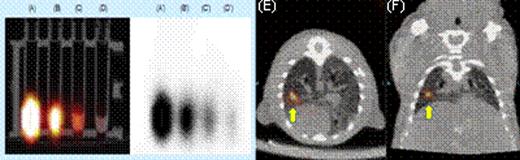

We first tested whether commercially available nanoparticles can be electro-transferred into cultured and primary human T cells. 43 nm diameter latex nanoparticles and 7 nm gold nanoparticles (GNPs) were electro-transferred into T cells and visualized by TEM and confocal imaging (Figure 1). We have modified GNPs on the surface with the chelator, diethylenetriaminepentaacetic acid (DTPA), for stable coordination with 111In followed by GNP PEGylation. We have shown that these radiolabeled GNPs can be readily electro-transferred into T cells suitable for combined single-photon emission computed tomography (SPECT) and computed tomography (CT) (Figure 2). We used a clinical SPECT/CT scanner to detect 111In-GNP in T cells (∼2.1 × 104 nanoparticles/cell) at a sensitivity of ∼760 cells/mL. After developing electroporation protocols of nanoparticles and in vivo imaging of 111In-GNPs, additional sensitivity was achieved by modifying the chelating chemistry using the macrocyclic chelator, 1,4,7,10-tetraazacyclododecane-1,4,7,10-tetraacetic acid (DOTA), to bind 64Cu to GNPs, increasing the number of gold particles/cell, and using 64Cu-labeled GNPs for imaging by positron emission tomography (PET). Before tail vein injection to a mouse, 11.4 mCi was detected from 10 million T cells (suspended in 300 μL PBS) electroporated using a BTX ECM830 device with the following settings: 1 kV/cm, 4 ms duration, single square pulse (Figure 3). The estimated concentration of nanoparticles transferred into T cells was ∼2.3 × 105 nanoparticles/cell as determined by a gamma counter (2470 Wizard, PerkinElmer) and nanoparticle titration. While 20 nm GNPs were used for 111In labeling, 7 nm GNPs were chosen for 64Cu labeling because of the improved (10-fold) electroporation efficiency.

Figure 2.

SPECT Imaging. (A) through (D) show the radioactivity of electro-transferred 111In-GNPs into T cells. (E) axial and (F) coronal views of directly injection of T cells containing111In-GNPs.